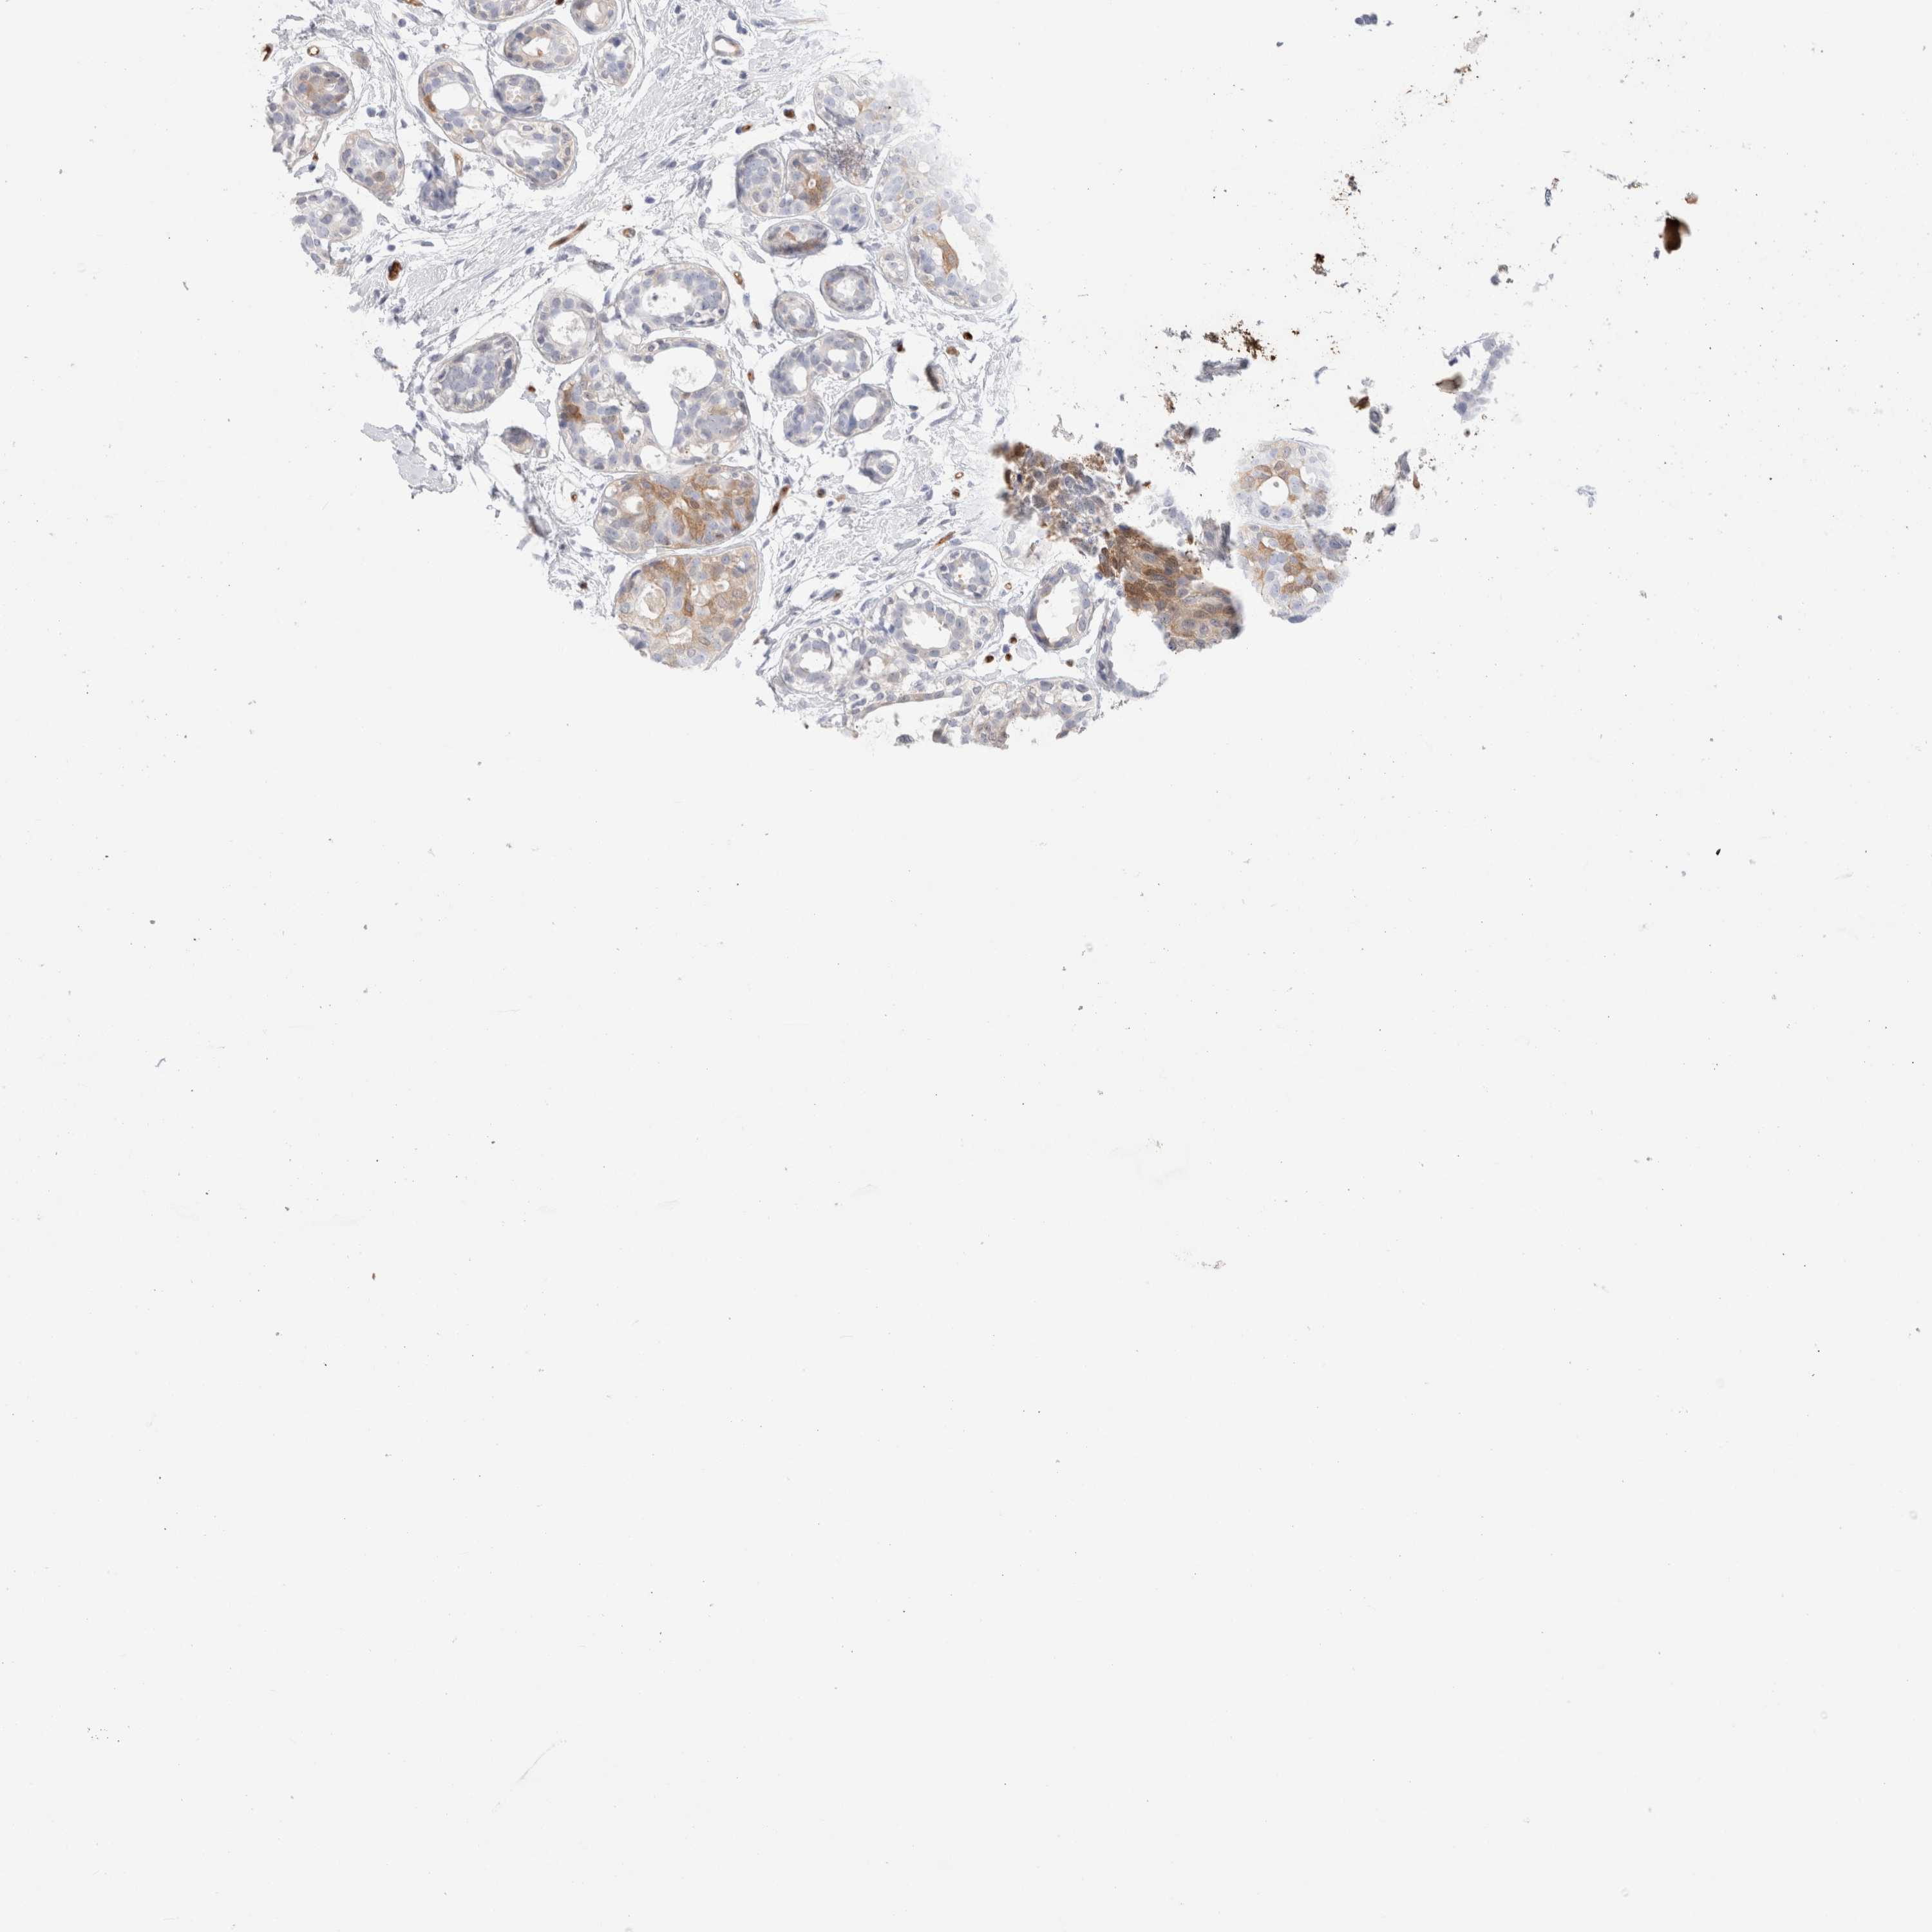

CANCER BREAST CANCER Show tissue menu

BRCA TCGA BRCA VALIDATION PROTEIN EXPRESSION

Breast cancer

Human cancer